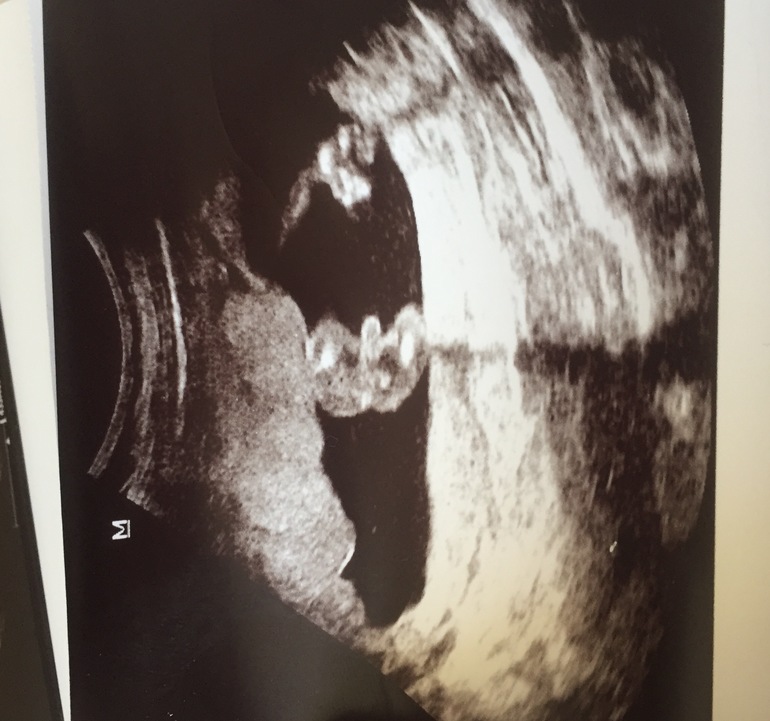

Доброе утро! Девочки, может кто сможет подсказать пол по фото узи! Буду очень благодарна. Дело в том, что сказали, что будет мальчик, но женщина одна уверяет , Что будет девочка по календарю, который ей никогда не лукавил. Хоть это банально и глупо , но я все равно не на шутку задумалась,хотя понимаю, что узи в наше время достовернее.Срок 16 недель и 4 дняКатерина

у меня календарь слукавил,по нему мы ждали девочку. не верьте. мальчишка у вас.

Мальчик у вас!) поздравляю, легкой беременности 🌷

Я уже задумалась, точно ли на 1 фото писюн)) перелопатила сообщества, кто-то говорит могут перепутать с пуповиной

Вот она?) красным обвела в кружочек?)